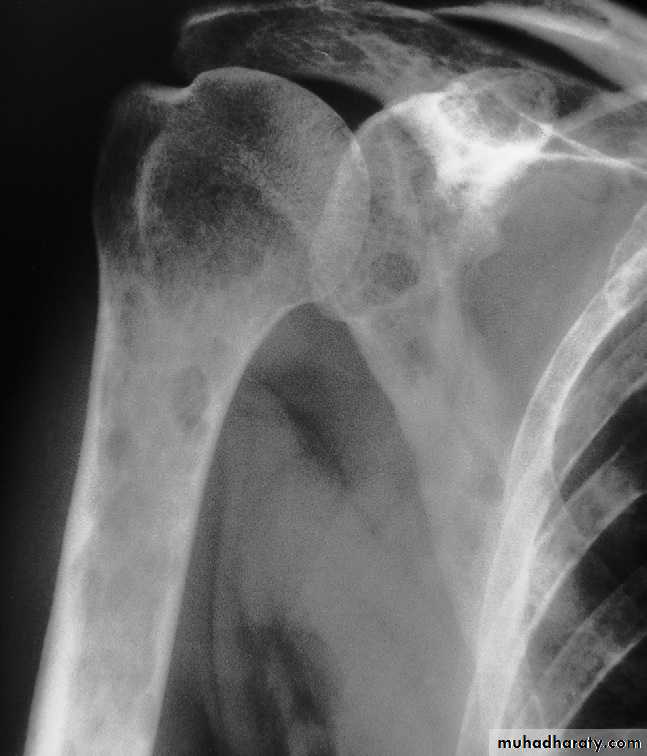

Hyperparathyroidism:

Excess parathyroid hormone secretion mobilizes calcium from the bones , resulting in a decrease in bone density , it may be primary from hyperplasia or tumour of the parathyroid glands or secondary to chronic renal failure. generalized loss of bone density.

. subperiosteal bone resorption.

. soft tissue calcification.

.brown tumour.